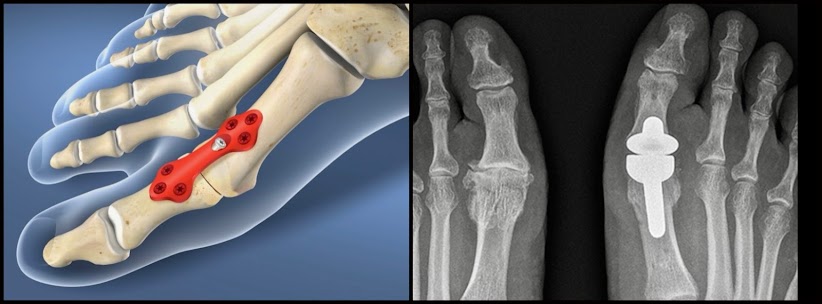

If the arthritis is more advanced the options are usually either to fuse the joint so it no longer moves, and is therefore in longer painful, or to do a joint replacement. There are pros and cons to each if these options and you will need to discuss your individual situation with a surgeon.

![]() |

| Joint Fusion Joint Replacement |

If the toe is angled or if you have painful bunion then the surgery will need to try and correct the deformity. There are many different procedures that surgeons can choose from but one of the more common ones is the Scarf and Akin Osteotomy where the surgeon uses precise cuts to remove sections of bone and then titanium screws to correct the toe position.

| Scarf & Akin Osteotomy |